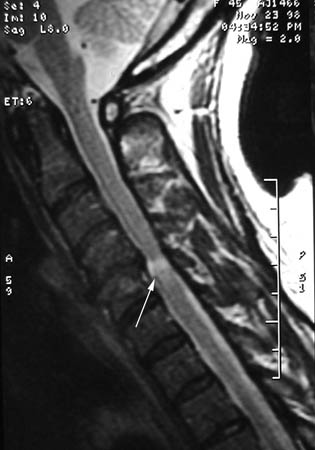

[Figure caption and citation for the preceding image starts]: A single level of spinal cord compression with T2 changes, on cervical sagittal T2 sequence in the presence of symptomatic degenerative cervical myelopathyDennis A. Turner, MA, MD [Citation ends].